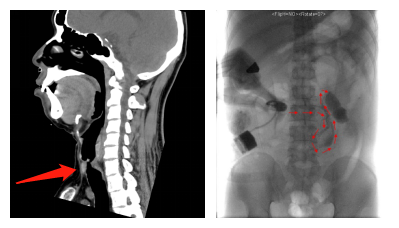

清华长庚多科室协作 围剿迷路气道的汤圆